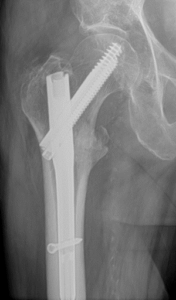

Acute fracture care of the pelvis and the extremities